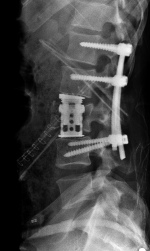

Arthrodèse lombaire antérieure

Cette intervention est proposée en cas de discopathie invalidante, ou en complément d'une arthrodèse postérieure.

Laminectomie et arthrodèse

En cas de Sténose lombaire associée à un Spondylolisthesis